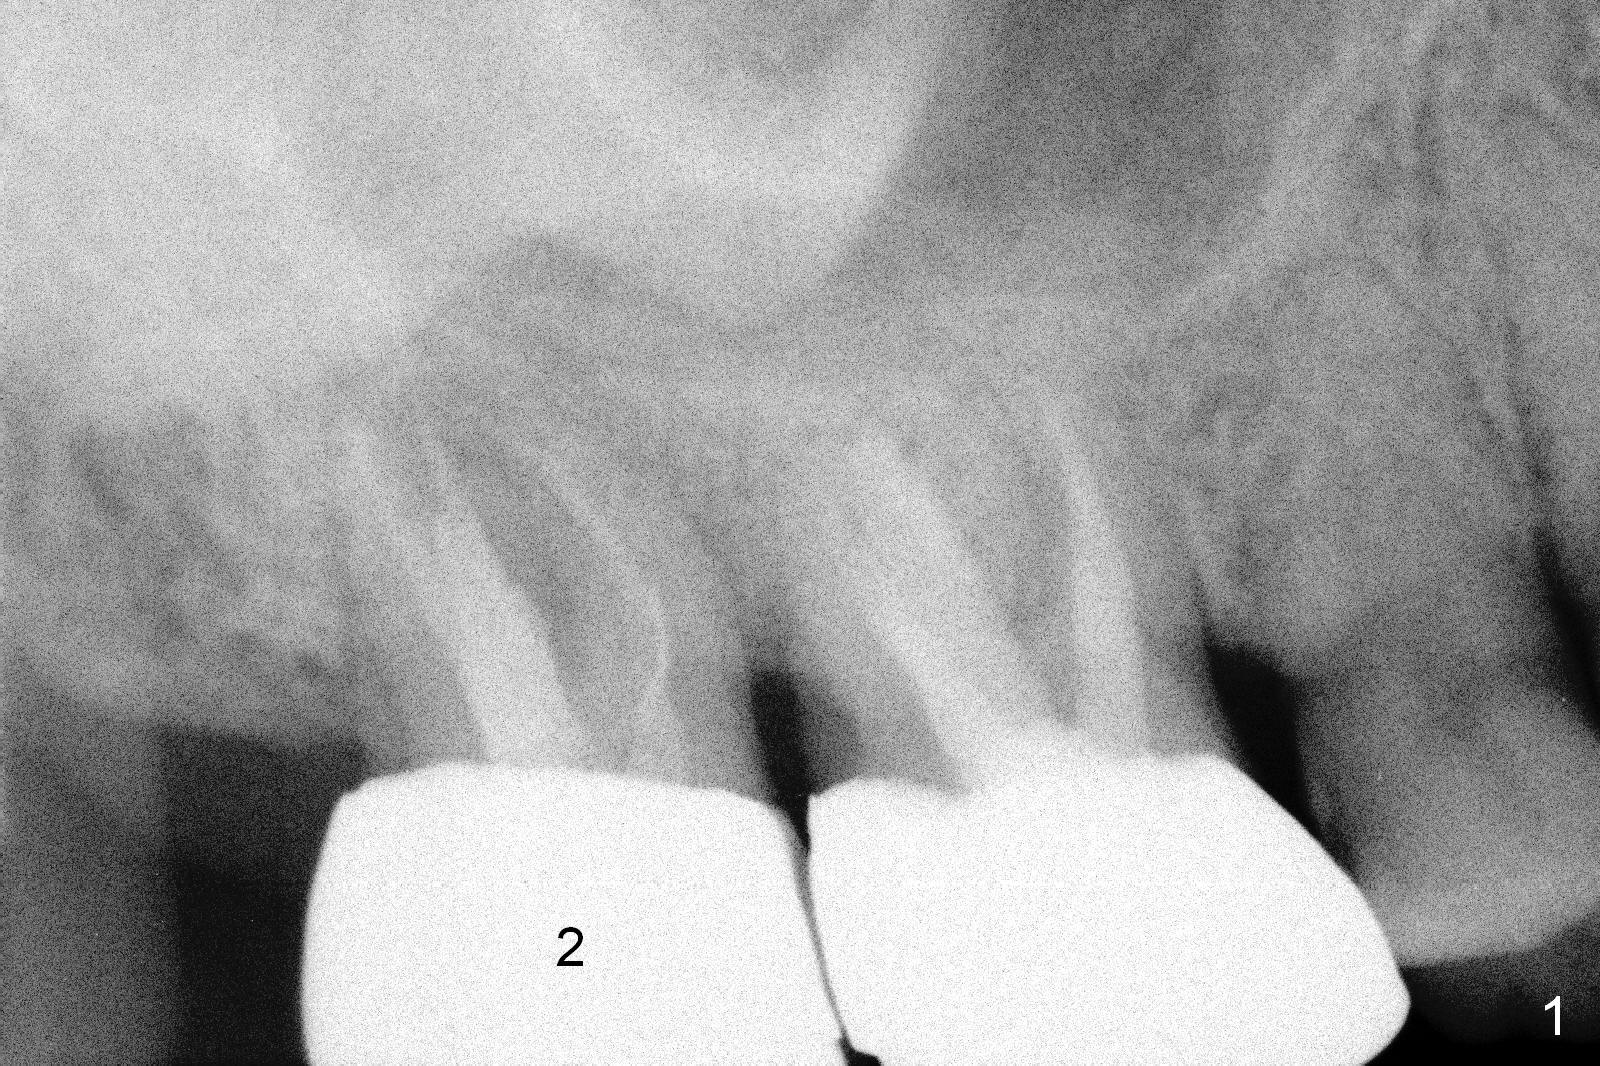

A 59-year-old man is a bruxer, fracturing the teeth #8 and 9.  Now the tooth #2 seems to have fractured (Fig.1).  Since the apices appear to protrude into the sinus, either 7x14 mm tissue-level (Fig.2) or 6.9x10 mm bone-level (Fig.3) implant will most likely penetrate the sinus floor (red dashed line).  To protect the sinus membrane, PRF membrane or plug (blue curved line) is to be placed prior to bone graft (yellow circles) and implant placement.  Prepare Magic Expanders and Magic Sinus Lifter.  Clindamycin will be used after extraction.  Since the roots of the upper 2nd molar usually fuse, prepare large gauzes for hemostasis.  Check the buccal and palatal walls for any defect.  Start osteotomy away from the defective wall.  Place the remaining PRF membrane for wall repair before bone graft.  Set stopper 2 mm short of the intended bone-level implant length.